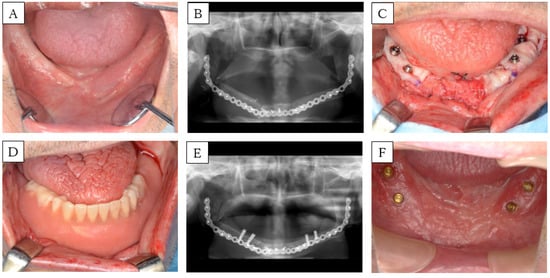

3.3. Case 5 (Method 3)